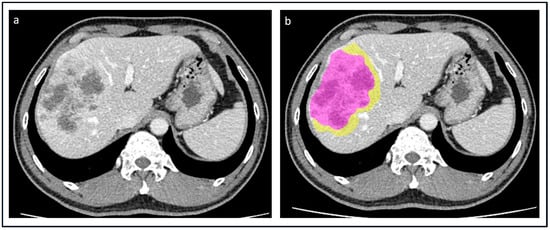

2.2. Imaging Acquisition, Tumor Segmentation, and Radiomic Features Extraction